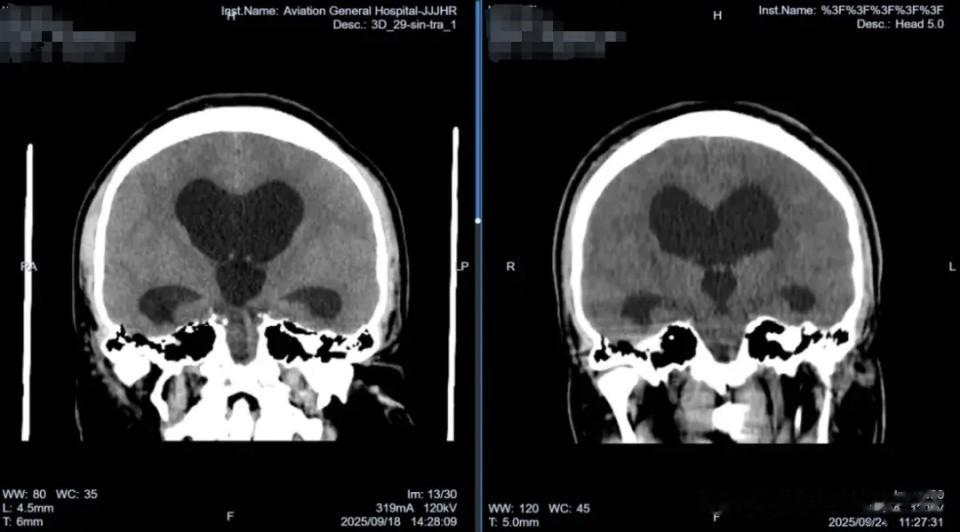

在精心治疗下,韦先生复查头颅CT显示脑室系统明显减小,脑脊液循环恢复通畅。出院时,韦先生的精神状态良好,头晕症状完全消失,更令他欣喜的是,他的视力保住了,视神经萎缩的情况得到有效控制。一个微小的骨孔,一次精准的内镜手术,挽救了一位年轻公职人员的视力和职业生涯。